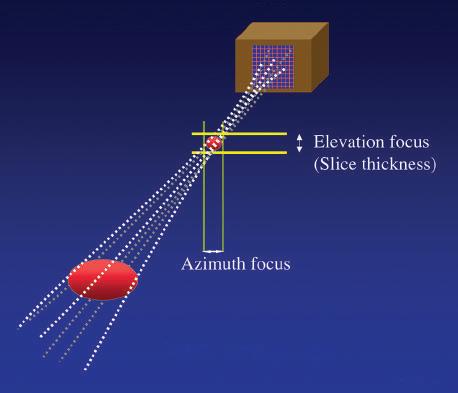

Two-Dimensional Arrays

Transducer arrays can be formed either by slicing a rectangular piece of transducer material perpendicular to its long axis to produce a number of small rectangular elements or by creating a series of concentric elements nested within one another in a circular piece of piezoelectric material to produce an annular array. The use of multiple elements permits precise focusing. A particular advantage of 2-D array construction is that the beam can be focused in both the elevation plane and the lateral plane, and a uniform and highly focused beam can be produced (Fig 1.15). These arrays improve spatial resolution and contrast, reduce clutter, and are well suited for the collection of data from volumes of tissue for use in 3-D processing and display. Unlike linear 2-D arrays, in which delays in the firing of the individual elements may be used to steer the beam, annular arrays do not permit beam steering and, to be used for real-time imaging, must be steered mechanically.

1.15 Two-Dimensional Array. High-density, two-dimensional (2-D) arrays consist of a 2-D matrix of transducer elements, permitting acquisition of data from a volume rather than a single plane of tissue. Precise electronic control of individual elements permits adjustable focusing on both azimuth and elevation planes.

In addition to axial resolution, resolution in the planes perpendicular to the beam axis must also be considered. Lateral resolution refers to resolution in the plane perpendicular to the beam and parallel to the transducer and is determined by the width of the ultrasound beam. Azimuth resolution, or elevation resolution, refers to the slice thickness in the plane perpendicular to the beam and to the transducer (Fig. 1.26). The width and thickness of the ultrasound beam are important determinants of image quality. Excessive beam width and thickness limit the ability to delineate small features and may obscure shadowing and enhancement from small structures, such as breast microcalcifications and small thyroid cysts. The width and thickness of the ultrasound beam determine lateral resolution and elevation resolution, respectively. Lateral and elevation resolutions are significantly poorer than the axial resolution of the beam. Lateral resolution is controlled by focusing the beam, usually by electronic phasing, to alter the beam width at a selected depth of interest. Elevation resolution is determined by the construction of the transducer and generally cannot be controlled by the user.